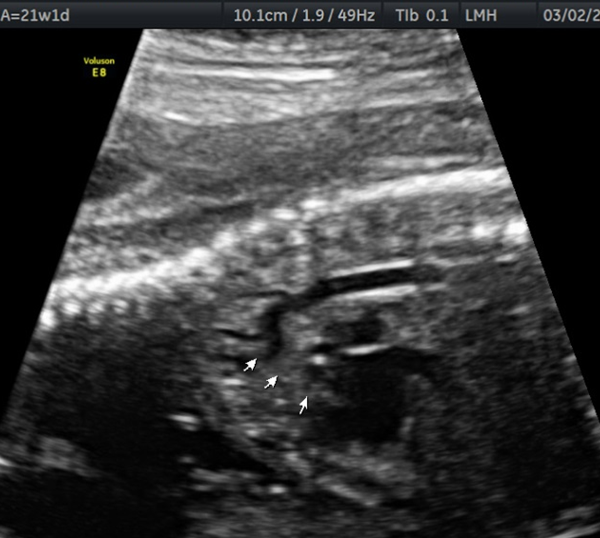

What are the US findings seen with Coarctation of the Aorta?

Left ventricle smaller than right ventricle

Bicuspid aortic valve, narrow area of the aorta

Coarctation of the Aorta